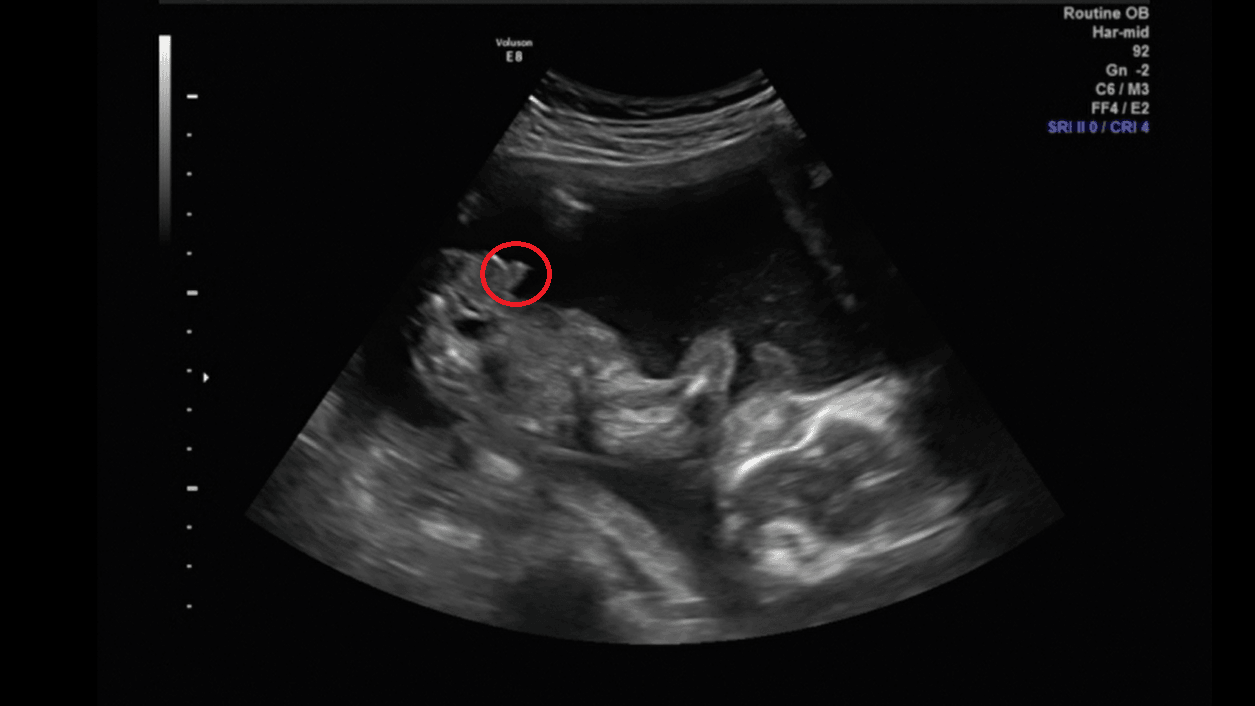

A najlepsze, że dopiero teraz kapnęłam się skąd lekarz wykonujący usg w pierwszych sekundach badania wiedział, że to chłopiec :p Mój bezwstydnik od razy po włączeniu sprzętu pokazał co ma między nóżkami [emoji5]

A najlepsze, że dopiero teraz kapnęłam się skąd lekarz wykonujący usg w pierwszych sekundach badania wiedział, że to chłopiec [emoji14] Mój bezwstydnik od razy po włączeniu sprzętu pokazał co ma między nóżkami [emoji5]

Chlopaki lipcowe okazuja sie byc bezwstydnymi...hihi .za to dziewczynki sie chowaja.